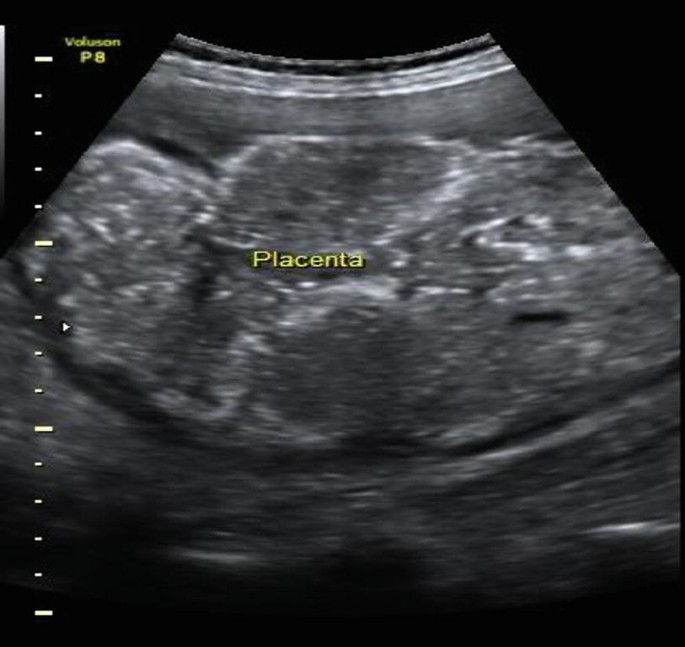

# **Antepartum Hemorrhage (APH): Causes, Symptoms, Diagnosis, Management and Complications**